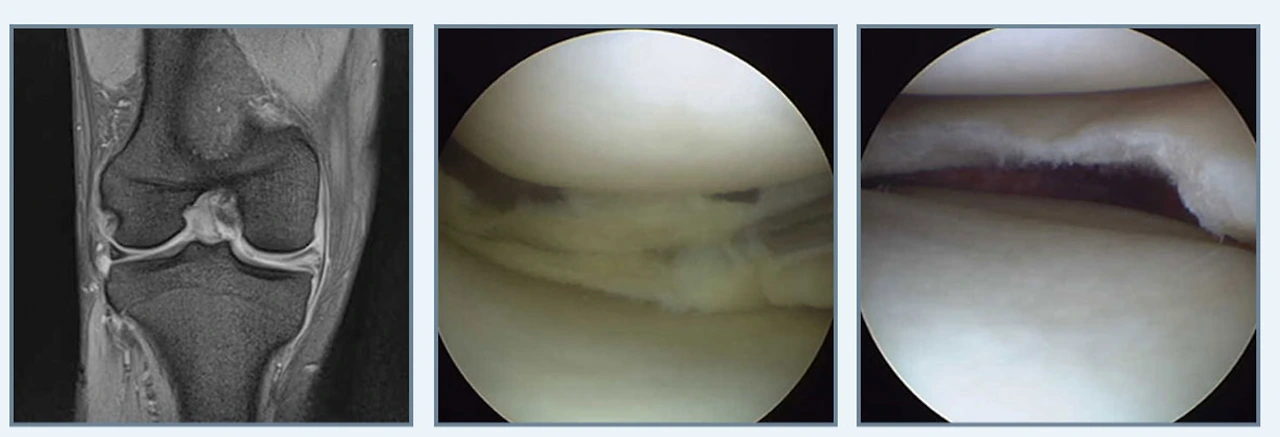

연골판 부분 절제술이란, 파열된 연골판 조직을 제거하고 온전한 연골판 조직을 보존해 기능하도록 하는 수술방식으로, 수평형 파열과 피판형 파열과 같은 파열 형태에 따라 수술이 진행됩니다.

연골판부분절제술.PNG

다음 연골판 봉합술은 연골판의 기능을 보존하기 위해 후각부의 파열을 봉합하는 것으로 체중을 가하거나 심한 운동을 할 경우에 재발할 수 있다는 단점이 있어 면밀한 검사가 필수입니다.

연골판봉학술.PNG

마지막 연골판 이식술은 파열된 반월상연골을 대신할 연골판을 이식하는 방법이지요.

연골판이식술.PNG